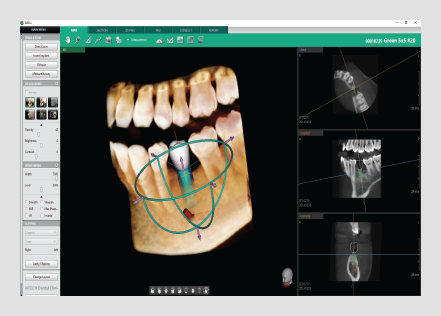

• Intuitive implant simulation tools for collision detection (implant/canal), bone density verification, and oblique viewing tools

• 3 click implant simulation

• Collision detection

• Bone density

• Oblique view mode

• 8 multi-section(curve)

management

• One-click cross section

(3D PAN tab)

• Canal drawing

• Colorized bone density viewing modes available

• Adjustable automatic implant collision detection function between multiple implants and/or nerve canal